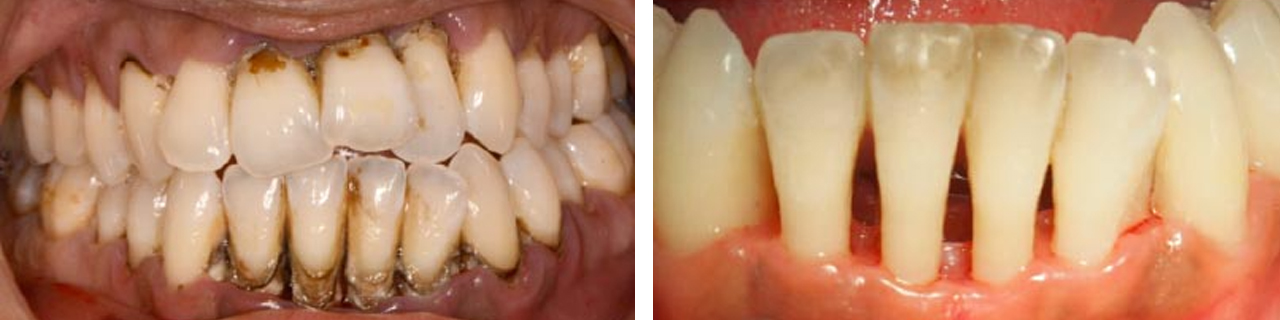

Periodontal

Eliminación de cálculo mediante raspado y alisado radicular.